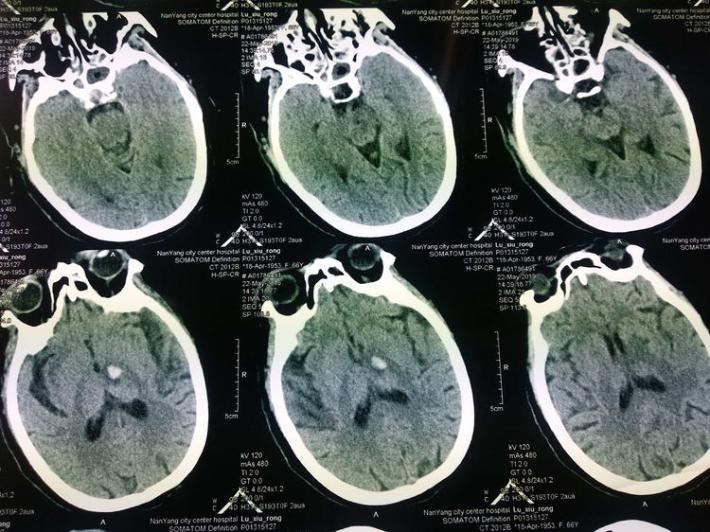

术后复查头部CT:左侧丘脑血肿无扩大,未见造影剂渗漏。

术后8天复查头部MRI

查体:患者神志清,精神可,双侧肢体肌力4级,NIHSS评分:4分,mRS:2分。